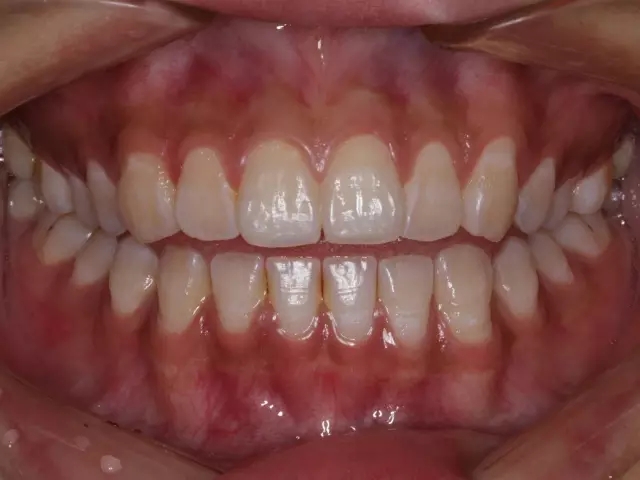

正位萌出到位,在牙尖交錯(cuò)位建立咬合關(guān)系,只是一個(gè)靜態(tài)的狀況??陬M系統(tǒng)的功能要靠運(yùn)動(dòng)來(lái)實(shí)現(xiàn),而一旦動(dòng)起來(lái),很多“看”似建立了正常咬合關(guān)系的智齒很可能會(huì)造成咬合干擾,給整個(gè)口頜系統(tǒng)帶來(lái)傷害。

這樣 “萌出到位有咬合” 的智齒應(yīng)該 拔掉